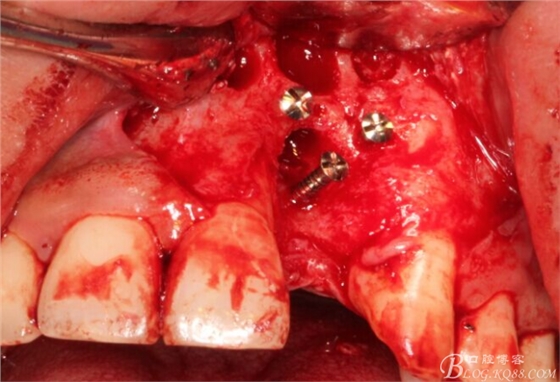

旋入一長兩短3顆鈦釘。

將自體骨與BIO-OOS骨粉混合植到術(shù)區(qū),蓋生物膜。